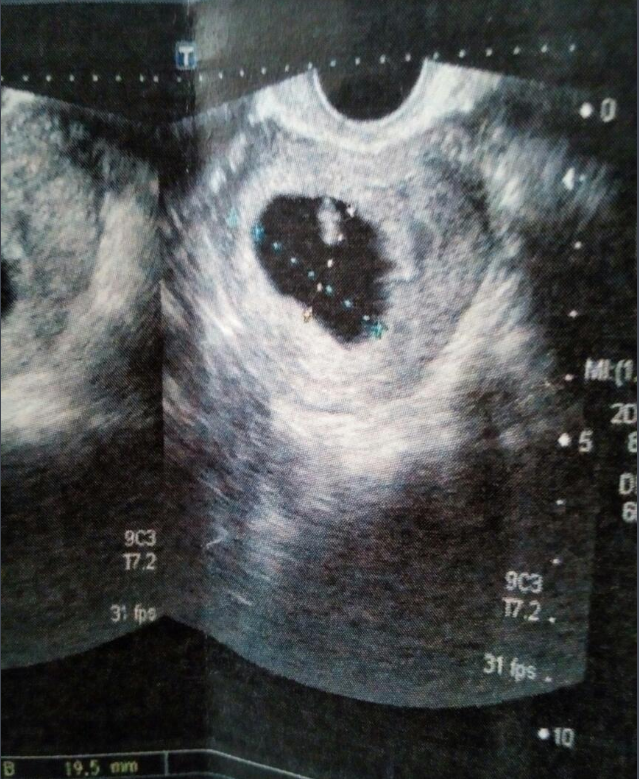

彩超是一种以超声波为主要扫描的技术检查,一般情况下,进行检查时所显现出来的图像是黑白的,而在黑白的基础上增加彩超技术就可以使其显现出来的图像有颜色。

其实彩超中的彩并不是我们想象中的五颜六色,它主要是以红色或者蓝色来表示身体中的血液,这可以帮助医生分辨血液的流动方向。

在检查时颜色越鲜亮,说明血液流动的速度就越快,而如果颜色越暗淡,则说明血液流动的速度就越慢。医生可以由此判断病人是否存在心脑血管疾病以及其他器官的血流情况。

医生能通过红色或者蓝色的标注来观察血管粗细并且判断是否存在病变,还能通过检查血液的流动来判断心脏是否存在问题。

彩超在检查时只是以红色或者蓝色显现出来,而检查出来的图像颜色并没有多大改变,更不会有想象中的五颜六色。